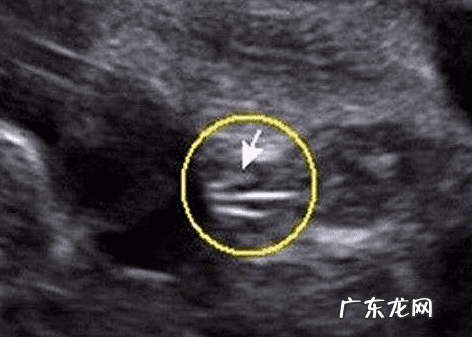

女宝宝的B超图:三条白线是明显的女宝宝特征,如果没有看到明显的三条白线就看两腿之间有没有突出的东西,并且中间有小凹槽的就是女宝宝 。